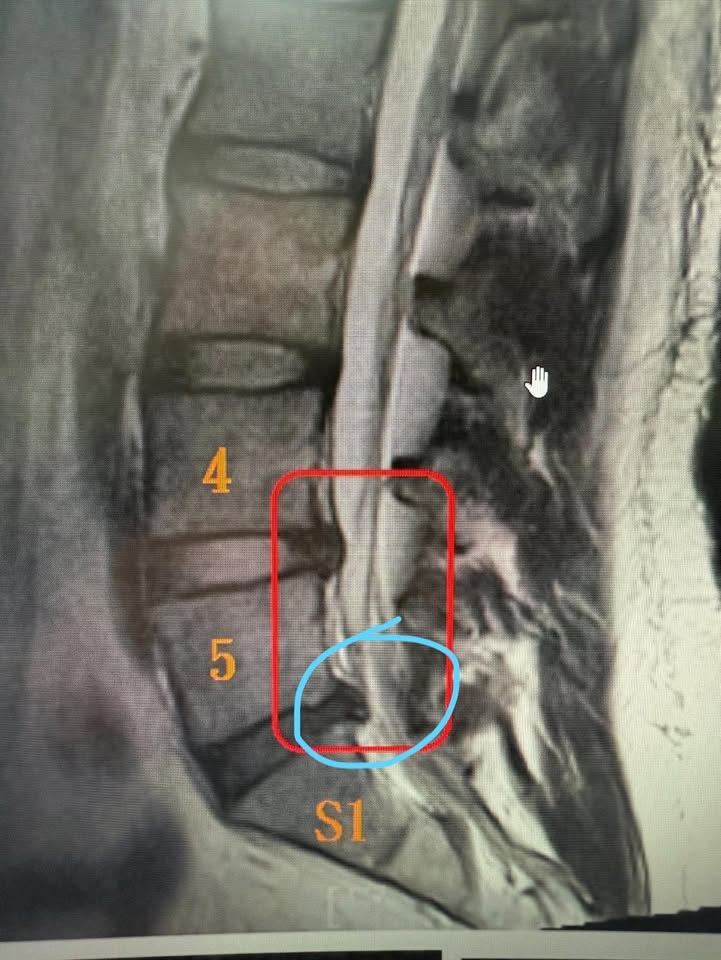

那天,她幾乎用盡全身的力氣才勉強走進我的診間。我仔細查看了她帶來的核磁共振影像,每一張切面都不放過。經過詳細分析後,我確認雖然她的椎間盤突出較為嚴重,但並未壓迫到馬尾神經,沒有大小便失禁,也沒有下肢無力等嚴重神經損害的表現。看著她略帶恐懼的眼神,我輕聲地說:「陳小姐,我知道妳現在很痛,但妳還沒到非開刀不可的地步。妳還年輕,我們可以試試非手術治療,讓妳恢復正常生活。」